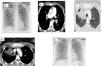

A 20-year-old woman, non-smoker, was admitted to our department presenting sudden onset of dyspnea. Her medical history included oral contraceptive use three months ago. Basic laboratory tests showed elevated D-dimers levels. Chest radiograph demonstrated pulmonary infiltrates in the right upper field (Fig. 1A). Further imaging evaluation using CTPA showed filling defects in both main pulmonary arteries, all lobar and segmental arterial branches except in right upper lobe arteries as well as ground glass opacities in the right upper lobe (Fig. 1B–D). These findings were compatible with pulmonary embolism and associated focal pulmonary edema. No signs of right/left cardiac dysfunction were found on transthoracic echocardiography. The patient was treated with rivaroxaban for 3 months. Complete resolution of alveolar infiltrates was noted after 5 days of anticoagulation treatment (Fig. 1E).

(A) An admission chest radiograph showing pulmonary infiltrates (red arrows) in the right upper lung field. (B) A CT pulmonary angiography demonstrating filling defects in both main pulmonary arteries (red asterisk). (C) A CT pulmonary angiography demonstrating filling defects in lobar and segmental arterial branches. (D) A CT pulmonary angiography demonstrating ground glass opacities in the right upper lobe without filling defects in right upper lobe arteries. (E) A chest radiograph performed on the 5th day of hospitalization showing complete resolution of the focal pulmonary edema.